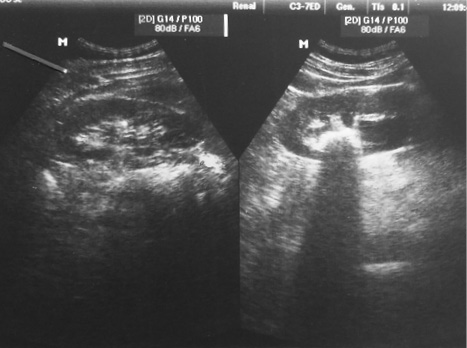

Ультразвуковое исследование. Размеры правой почки 106×39 мм, толщина паренхимы 17 мм, чашечно-лоханочная система (ЧЛС) не расширена. В нижней чашке обнаружен конкремент размером 6 мм, в средней — размером 5 мм. Размеры левой почки 112×47 мм, толщина паренхимы 15 мм, ЧЛС резко расширена. Обнаружены тени, присущие коралловидному камню, размерами 2,5×2,5 см в лоханке и 1,0×1,0 см в нижней чашке (рис. 1).

Рис. 1. Пациент Г.С. Данные ультразвукового исследования